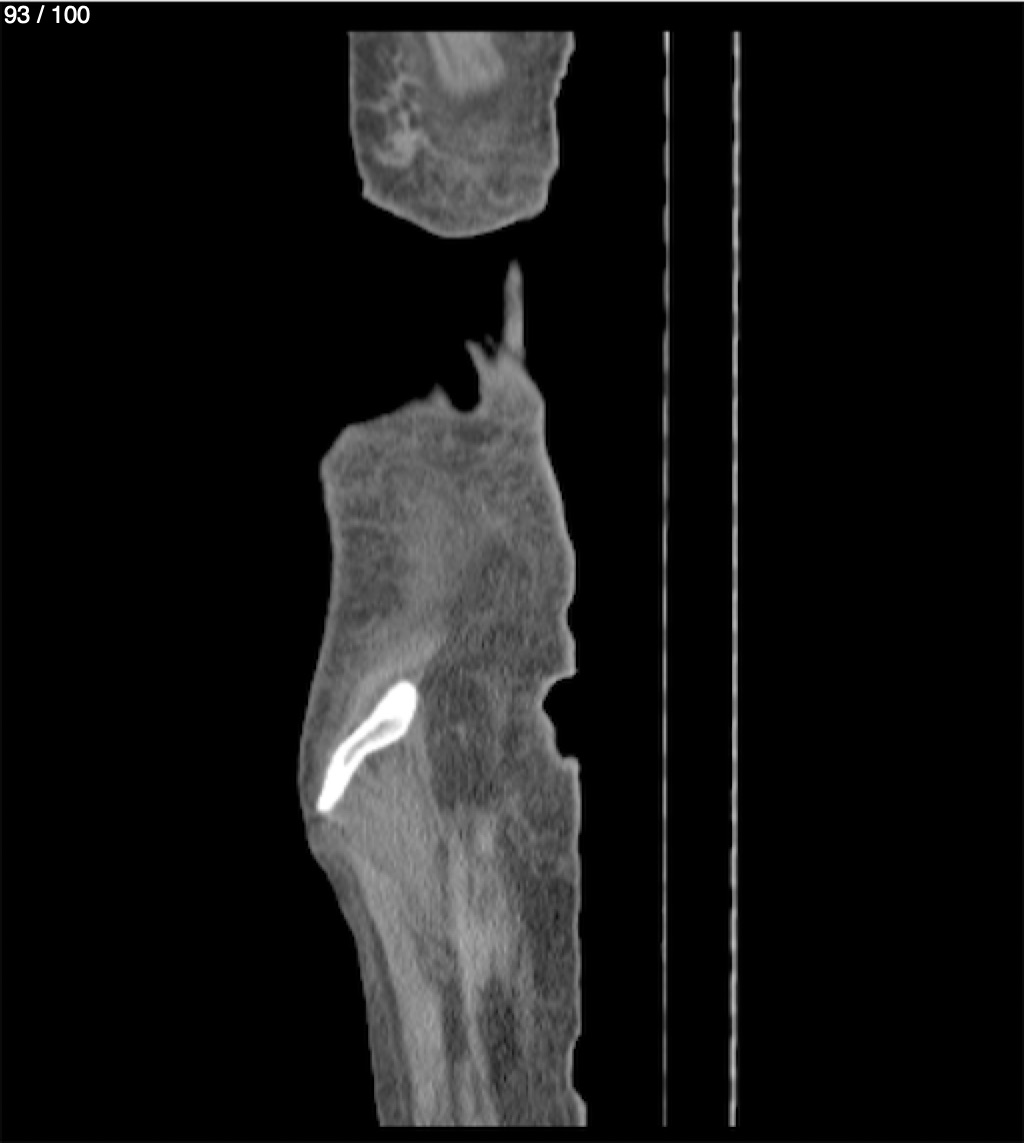

Hilda Geronimo Mendez 60A - T.C Abdomen Simple